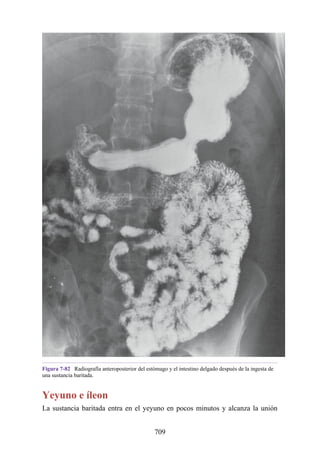

comprimirse contra la 1.a costilla para detener una hemorragia mortal. La tercera porción de la

arteria axilar puede notarse en la axila, ya que se localiza anterior al músculo redondo mayor